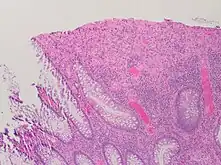

A micrograph demonstrating cryptitis, a microscopic correlate of colitis. H&E stain.

An important investigation in the assessment of colitis is biopsy for histopathology. A very small piece of tissue (usually about 2mm) is removed from the bowel mucosa during endoscopy and examined under the microscope by a histopathologist. A biopsy report generally does not state the diagnosis, but should state any presence of chronic colitis, give an indication of disease activity, as well as state the presence of any epithelial damage (erosions and ulcerations).[4]